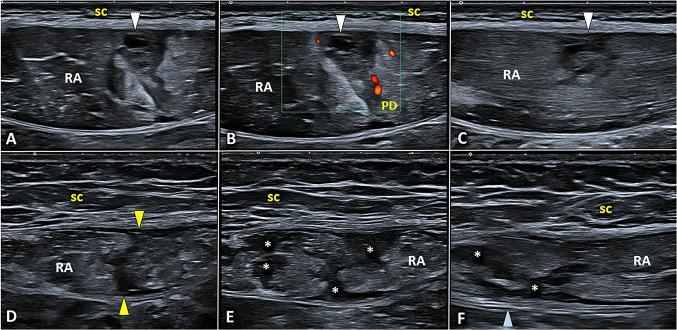

Padel is a racket sport, combining high-frequency and low-intensity athletic gestures, that has been gaining growing scientific interest in recent years. Musculoskeletal injuries are very common among padel players with an incidence rate of 3 per 1000 h of training and 8 per 1000 matches. To the best of our knowledge, a comprehensive collection describing the most common sonographic findings in padel players with musculoskeletal injuries is lacking in the pertinent literature. In this sense, starting from the biomechanical features of padel-specific gestures we have reported the ultrasonographic patterns of most frequent injuries involving the upper limb, the trunk, and the lower limb. Indeed, comprehensive knowledge of the biomechanical and clinical features of musculoskeletal injuries in padel is paramount to accurately perform a detailed ultrasound examination of the affected anatomical site. So, the present investigation aims to provide a practical guide, simple and ready-to-use in daily practice, to optimize the sonographic assessment of padel players by combining it with the clinical findings and the biomechanical features of athletic gestures.